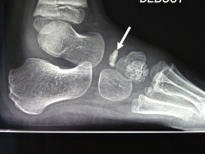

Exemple d'ostéochondrite de l'os scaphoïde (naviculaire) chez un garçon de 5 ans:

Les deux photos de gauche montrent un os densifié et aplati sur le pied gauche.

Les deux photos de droite montrent les mêmes radios sur le pied droit sain.